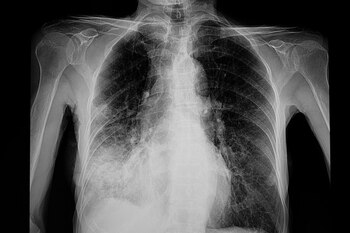

Pero hay otros dos tipos: la peste septicémica, que se propaga por todo el cuerpo, y la peste neumónica, que infecta los pulmones.

La peste neumónica, que causó la muerte en Arizona, también es la más fácil de propagar, según AP .